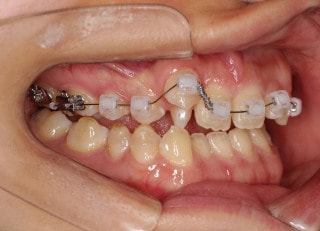

治療開始時